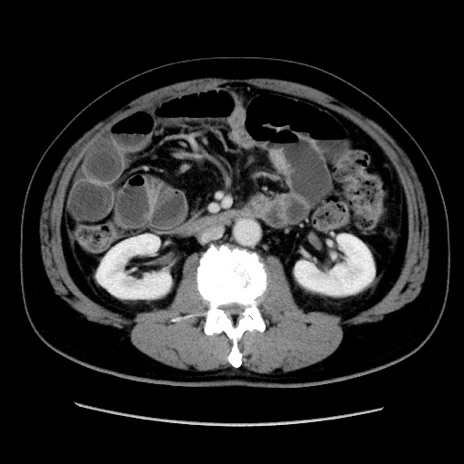

症例16(横断像)

【症例】 70歳代男性

【主訴】 腹痛、嘔吐

【現病歴】 約1ヶ月前より間欠的に腹痛と嘔吐あり、当院消化器内科を受診したところCTで多発する肝臓のLDAを指摘され、精査中であった。以降は消化器症状は安定していたが、2日前より嘔気と腹痛があり、同日より排便・排ガスが消失した。改善認めず、 本日、救急外来を受診した。

【既往歴】 大腸ポリープ切除後。

【身体所見】意識清明・会話良好、BT 36.3℃、BP 127/80mmHg、 P 80bpm、腹部:膨満あり、平坦・軟、上腹部正中および下腹部正中に圧痛あり、反跳痛なし、筋性防御なし。

【データ】WBC 7200、CRP 0.77